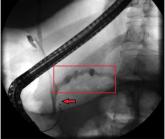

ArticlePancreatitis: The great masquerader?Author:Nicholas S. Duca, MDPublish date: October 1, 2018Pancreatitis, panniculitis, and polyarthritis syndrome mimics rheumatologic disease, often presenting without abdominal pain.Read More